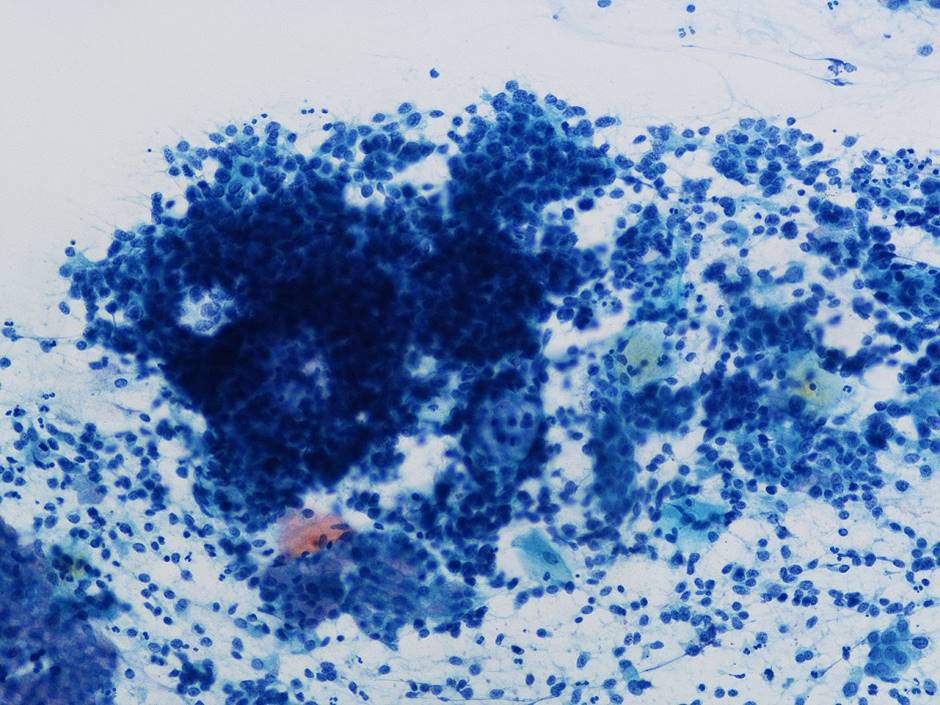

細胞診所見

背景に壊死物質は認められなかった。その中に偏在性核で核クロマチン増量を示す腺系異型細胞の不整形集塊を認めた。柵状配列や腺管構造もみられ上皮内腺癌を疑う細胞と考えた。またN/C比が高く細顆粒状の核クロマチンを有する傍基底型核異常を疑う細胞もみられた